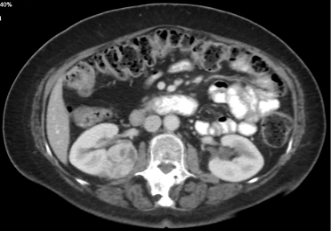

A female in her 70s was found to have a 4.5 cm incidental right, posterior, medial, hilar, endophytic, renal mass on imaging performed for abdominal pain. Her past medical history was notable for stroke, atrial fibrillation, dyslipidemia, arthritis, glaucoma, and she had an eGFR of 93 mL/min. She was on apixaban, gabapentin, and a statin at baseline.

Figure 1. A 4.5 cm right, posterior, medial, renal mass suspicious for renal cell carcinoma. Source: NYU Langone Health.

Based on the appearance of imaging (Figure 1), she was advised that this mass most likely represents a malignancy and the standard treatment is surgical removal. This can be done either through partial nephrectomy, in which the tumor and a portion of surrounding tissue is removed while the remaining, ipsilateral kidney is preserved, or radical nephrectomy in which the entire tumor-bearing kidney is removed.